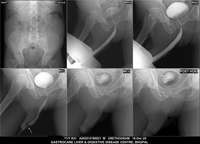

Section: URETHROGRAM

Total: 95 Cases